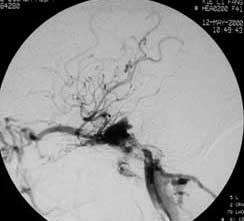

血管内栓塞对于单支或少数供血动脉的AVM,特别是新近出血的病例,可以达到微侵袭、痛苦小、疗效迅速的目的。

近来改变栓塞方式,将导管直接放置 畸形血管团内,注射NBCA胶,可使畸形团的解剖 治愈率提高至27%。再加上更细、超滑的微导管问世,栓塞的并发症更为降低。针对大型、功能区 的AVM栓 塞可缩小其体积,改善血液动力学分布,以利于显微外科技术切除或放射外科治疗,是后二者的重要辅助手段。